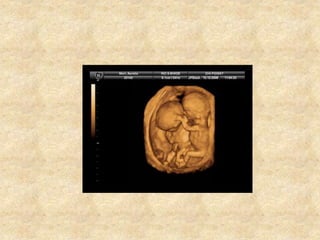

• Mode 3D permet balayage automatique ,

acquisition de volume d’échos dont le

traitement informatique dans tous les plans

de coupe .